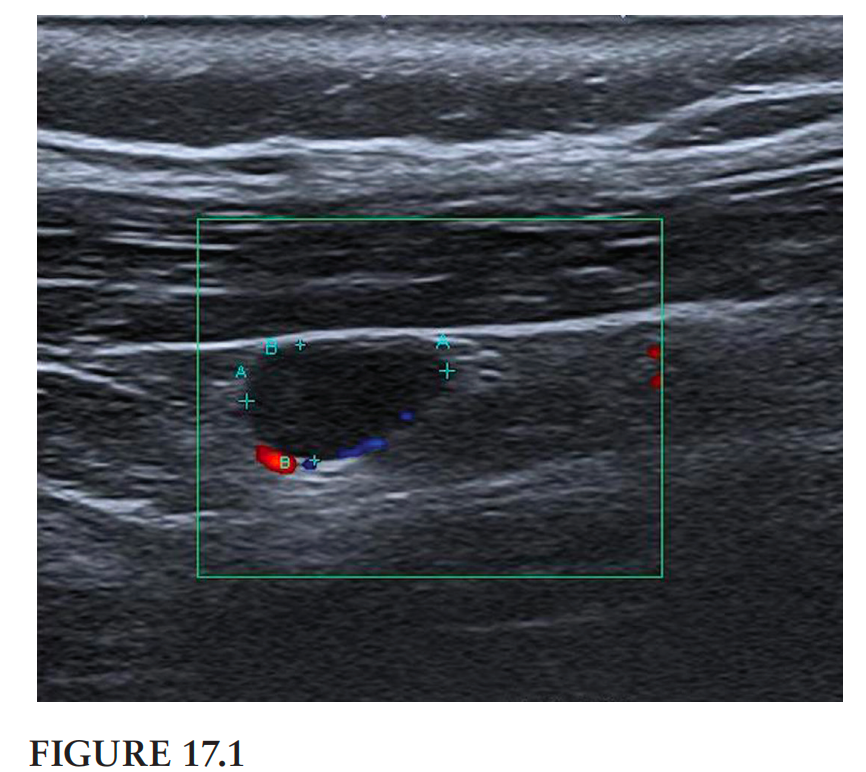

翻译:祁海丽;校对:石慧17 This ultrasound image (Figure 17.1) shows the midcervical region...